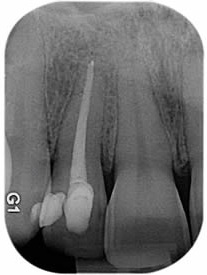

СЛИКЕ